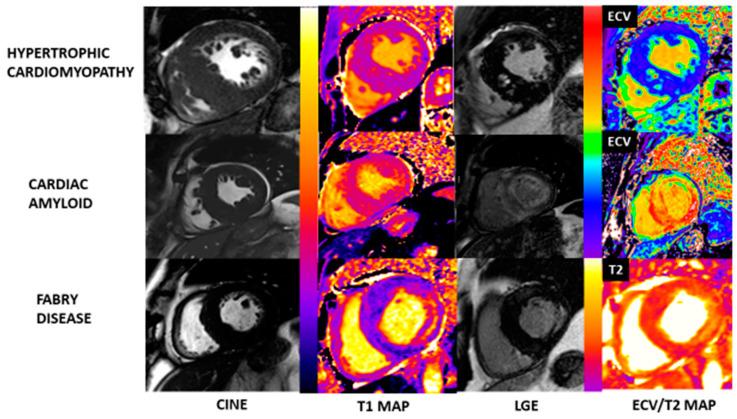

Hypertrophic cardiomyopathy (HCM) is characterized by abnormal growth of the myocardium with myofilament disarray and myocardial hyper-contractility, leading to left ventricular hypertrophy and fibrosis. Where culprit genes are identified, they typically relate to cardiomyocyte sarcomere structure and function. Multi-modality imaging plays a crucial role in the diagnosis, monitoring, and risk stratification of HCM, as well as in screening those at risk. Following the recent publication of the first European Society of Cardiology (ESC) cardiomyopathy guidelines, we build on previous reviews and explore the roles of electrocardiography, echocardiography, cardiac magnetic resonance (CMR), cardiac computed tomography (CT), and nuclear imaging. We examine each modality's strengths along with their limitations in turn, and discuss how they can be used in isolation, or in combination, to facilitate a personalized approach to patient care, as well as providing key information and robust safety and efficacy evidence within new areas of research.

肥厚型心肌病(HCM)的特征是心肌异常生长,伴有肌丝排列紊乱和心肌过度收缩,导致左心室肥厚和纤维化。在确定致病基因的情况下,它们通常与心肌细胞肌节的结构和功能有关。多模态成像在HCM的诊断、监测和风险分层以及筛查高危人群方面发挥着关键作用。继欧洲心脏病学会(ESC)首部心肌病指南近期发布之后,我们在以往综述的基础上,探讨心电图、超声心动图、心脏磁共振成像(CMR)、心脏计算机断层扫描(CT)和核成像的作用。我们依次审视每种模态的优势及其局限性,并讨论如何单独或联合使用它们,以促进个性化的患者护理方法,同时在新的研究领域提供关键信息以及有力的安全性和有效性证据。